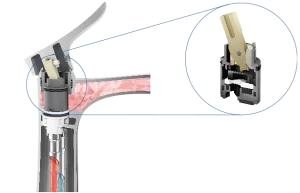

Vòi chậu gật gù nóng lạnh GO